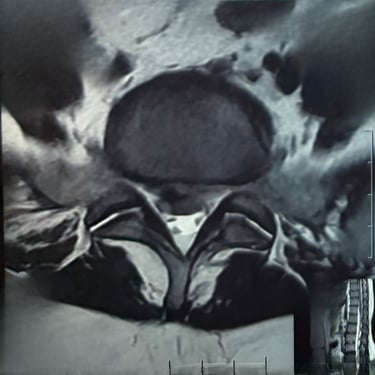

Manejo quirúrgico de la hernia lumbar con inestabilidad: enfoque moderno con FTP y TLIF

La hernia lumbar con inestabilidad vertebral es una patología frecuente que causa dolor lumbar persistente, ciática y limitación funcional, afectando la calidad de vida del paciente. Cuando el tratamiento conservador no logra resultados adecuados, la cirugía se convierte en la mejor opción terapéutica. La fijación transpedicular con tornillos (FTP) junto con la técnica TLIF (Transforaminal Lumbar Interbody Fusion) permite estabilizar la columna, descomprimir las estructuras nerviosas y lograr una adecuada fusión ósea. Este abordaje, especialmente mediante técnicas mínimamente invasivas (MISS), ofrece múltiples beneficios, como menor daño muscular, menor dolor postoperatorio y recuperación más rápida, facilitando el retorno temprano a las actividades cotidianas con mejores resultados clínicos.